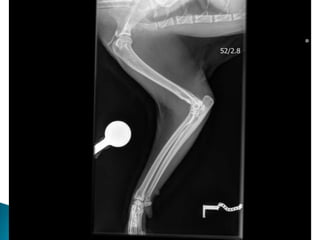

 Radiographs ***

 Radiographs

 Viral Testing- negative  Joint Culture  Cytology  Radiographs ***  Ultrasound Abdomen

• #10 He had smooth recovery from anaesthesia and seemed much more comfortable on his methadone. Cytology and Culture both were negative. Hocks and elbows to have increased WBC, predominately neutrophilic inflammation (91- 94%). Mild toxic change to the neutrophils. The right and left stifle: Low Neutrophils (< 1 x10e9/l). The majority of cells present were large mononuclear cells (85 - 87%). Immune mediated hypersensitivity type III reaction. Run through the types… I = hay fever idea – IgE released. II = IMHA like whereby antibody binds to cell surface antigen III = Antibody binds to cell suface antogen however these are solvent in blood and not attached to cells and so can settle out in various locations throughout the body. Periosteal proliferative polyarthritis occurs most often in male cats (intact and castrated), but female cats can also be affected. Cats of any age can develop this polyarthritis, but it is most common in young adults. Affected cats experience fever, lethargy, a stiff gait, and joint pain and swelling, particularly of the carpus and hock. There is sometimes concurrent edema of the skin and soft tissues overlying the joints. Lymph node hyperplasia may cause severe regional lymphadenopathy. Synovial fluid analysis reveals a moderate-to-severe neutrophilic pleocytosis and culture is negative. Papers form the 1980’s actually found that 100% of cats with chronic progressive arthritis showed FSFV or antibodies to it. But is it just incidental because this virus in particular is found in normal cats also. It has been suggested that infection with FeLV or FIV-induced immunosuppression allows FeSFV to multiply in the joints of predisposed individuals. However in papers that I came across, surprisingly there isn't an increased incidence of FeLV or FIV in affected cats. It occurs more commonly in young, entire or castrated, male cats less than 5 years of age. Radiographic changes may not be evident for the first 10–12 weeks of illness and then early findings include periarticular soft tissue swelling and mild periosteal proliferation. This matache Koshka to a T being that after roughly two months of steroid effectiveness. An abnormally coarse trabecular pattern of the bones of affected joints. Over time, the periosteal proliferation worsens and extends beyond the confines of the joint, which may lead to ankylosis. Periarticular osteophytes, subchondral cyst-like lesions and periarticular erosions are evident. Calcification and erosion of bone may occur at the attachment of ligaments and tendons, causing painful lesions (enthesopathies).